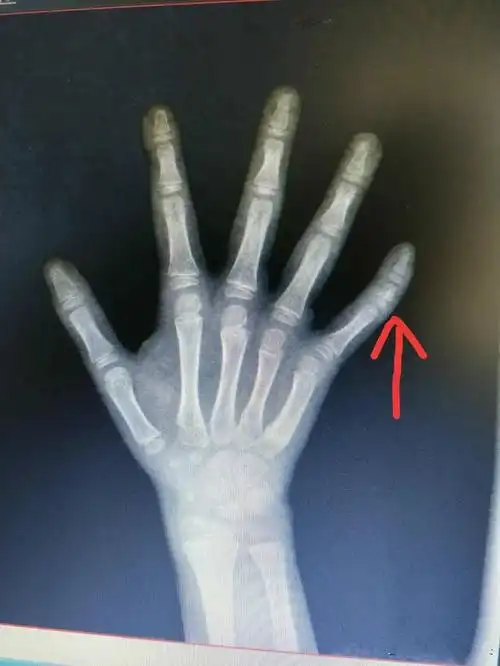

医生请帮忙认真看下骨骺线闭合没,非常感谢,顺便问一下,要怎么看?

应用生长激素的前提是骨骺没有闭合

长高#看身高要尽早,骨骺线完全闭合,就没翻盘机会了

骨骺线已近闭合

骨骺线未闭合

骨骺的闭合情况

如何确诊指骨骨骺早闭?